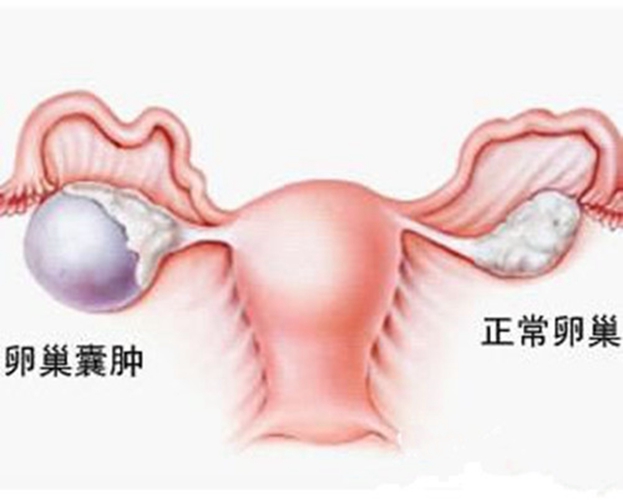

巧克力囊腫

右卵巢巧克力囊腫

右側卵巢囊腫

雙側巧克力囊腫

什麼是巧克力囊腫

A:巧克力囊腫也就是卵巢子宮內膜異位囊腫,它是由於異位的子宮內膜在卵巢內生生長,隨著月經多次樣出血,形成了一個存在陳舊性的積血囊腫,囊腫內容物一般像巧克力狀,所以稱為巧克力囊腫。引起內膜異位囊腫的原因現在不清楚,有許多的學說,最常聽到的就是子宮……

A:卵巢巧克力囊腫是子宮內膜異位症的一種,子宮內膜異位症包括巧克力囊腫、盆腔子宮內膜異位結節,以及子宮腺肌症。卵巢巧克力囊腫是經血逆流導致,經期會有經血逆流,如果逆流的經血種植在卵巢表面,定期剝脫、出血,逐漸增大就會形成巧囊,這與女性的特殊體質……